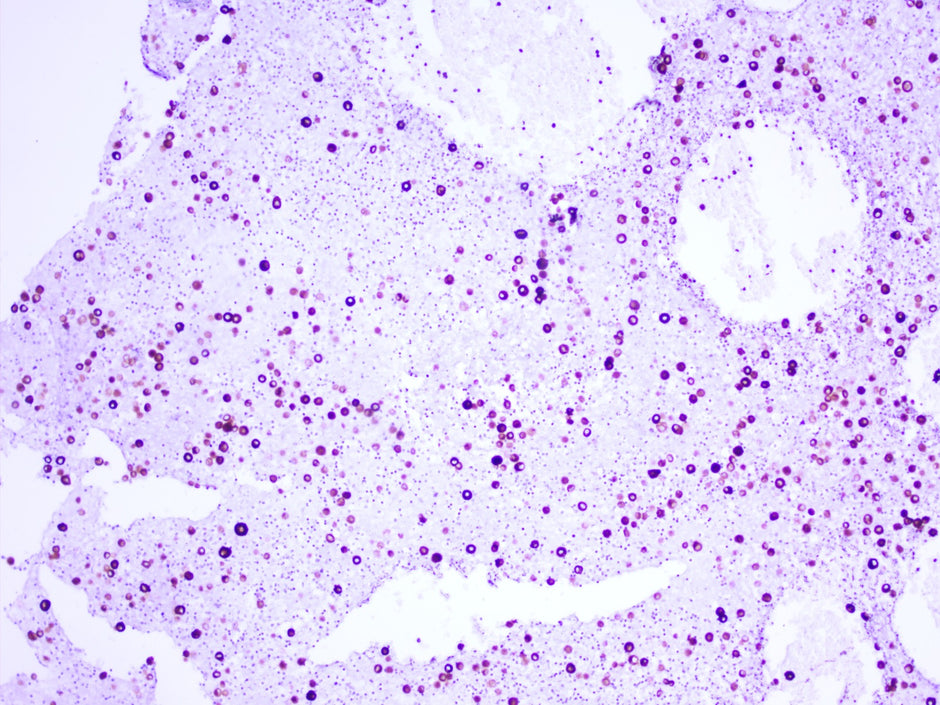

• Why is Kappa/lambda In-situ Hybridization Critically Acclaimed?

κ/λ原位杂交技术为何广受好评?

Kappa/Lambda 的检测方法 Kappa/Lambda的检测通常使用实验室中的四种方法进行:原位杂交、免疫组织化学、流式细胞术和 PCR。 原位杂交 κ/λ链探针试剂是用于原位杂交法的专用试剂。为了更准确、更灵敏地找到κ:λ mRNA序列,该试剂旨在特异性地靶向该基因。...